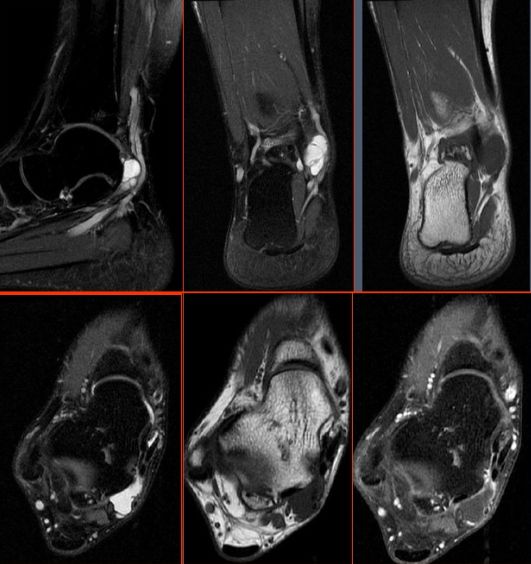

六、足底腱膜炎

足底腱膜是一个多层的纤维腱膜,由内层、中间层、外层构成,常说的腱膜通常指中间层,在MR上表现为2-4mm带状结构,在所有序列上为低信号。

足底腱膜炎是导致足底疼痛最常见的原因。

足底腱膜炎MRI表现:

足底腱膜炎伴跟骨内侧结节局限性水肿